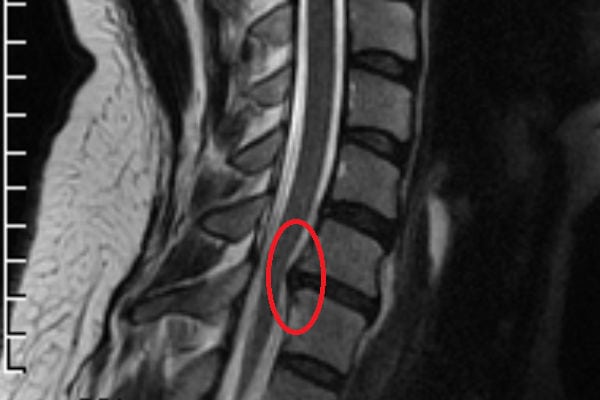

При неэффективности консервативного лечения в течение 1,5 месяцев проводится хирургическая операция для удаления межпозвоночной грыжи. При выборе методики хирургического вмешательства учитывают форму патологии, ее локализацию, стадию течения. Может быть устранено не только само выпячивание, но и поврежденный межпозвонковый диск. Даже при удалении межпозвоночной грыжи квалифицированным врачом есть вероятность послеоперационных нежелательных последствий.

Показания к удалению межпозвоночной грыжи любой локализации — корешковый синдром, дискогенная миелопатия, синдром позвоночной артерии с транзиторными ишемическими атаками, быстрое прогрессирование патологии. Такие тяжелые осложнения диагностируются примерно у 10-15% пациентов. Во всех остальных случаях смещение межпозвонковых дисков удается ликвидировать консервативными способами. Неврологи, вертебрологи рекомендуют больным хирургическое вмешательство только при полной неэффективности таблеток, физиотерапевтических процедур, ЛФК. Основная причина — вероятность послеоперационных осложнений:

Рецидив грыжи или появление протрузии диска

Так как пораженный двигательный сегмент не может выполнять прежние функции, то нагрузка ложится на рядом расположенные диски и позвонки. Они изнашиваются, уплотняются, истончаются, утрачивают стабильность. Итогом становится протрузия, а после смещения фиброзного кольца формируется новая грыжа.